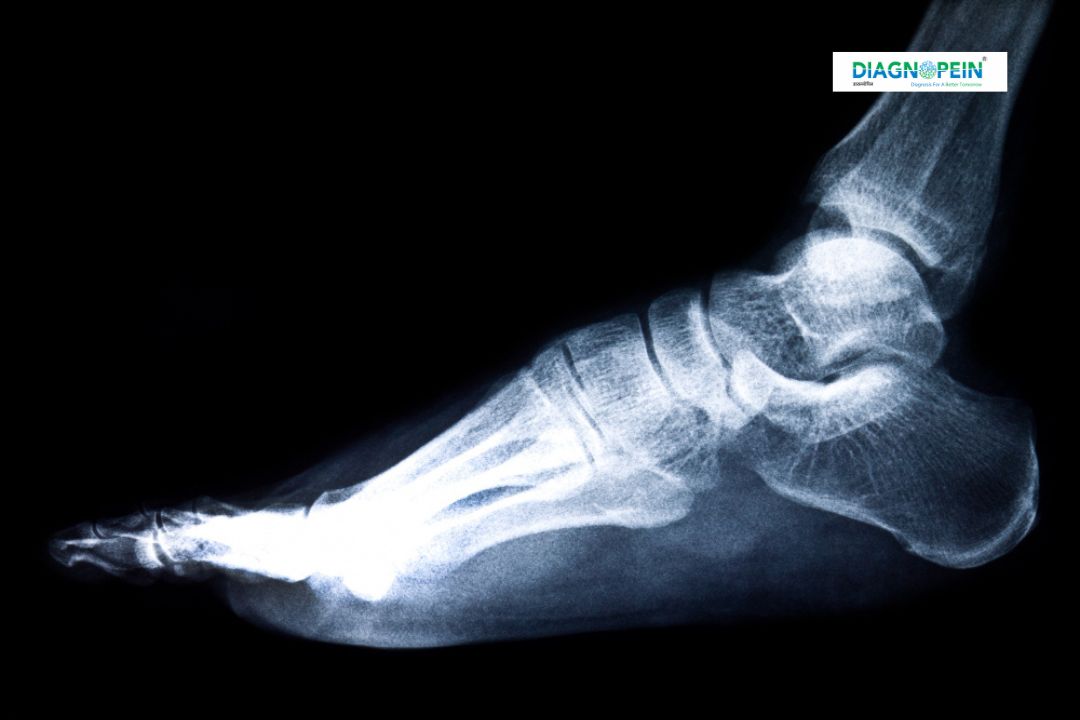

The X-Ray Left Foot AP (Anteroposterior view) is a detailed imaging test used to examine the bones and joints of your left foot. At Diagnopein Nashik, this test helps doctors assess injuries, deformities, joint disorders, and post-surgery bone healing with precision. Using advanced digital X-ray technology, we provide high-resolution images that support accurate and quick diagnosis, helping ensure better treatment outcomes.

Your foot plays a vital role in mobility, balance, and daily movement. Even minor pain or injury can affect your overall comfort and activity level. The X-Ray Left Foot AP in Nashik is important because it helps detect:

1. Fractures, bone cracks, or deformities.

2. Joint inflammation and arthritis.

3. Bone infections or tumors.

4. Foreign objects or bone misalignment.

5. Post-operative bone healing progress.

During an X-Ray Left Foot AP, several key parameters and structures are evaluated:

1. Bone alignment and density.

2. Fractures, cracks, or dislocation.

3. Joint spacing and cartilage condition.

4. Signs of infection or degenerative disease.

5. Foreign objects or bone abnormalities.